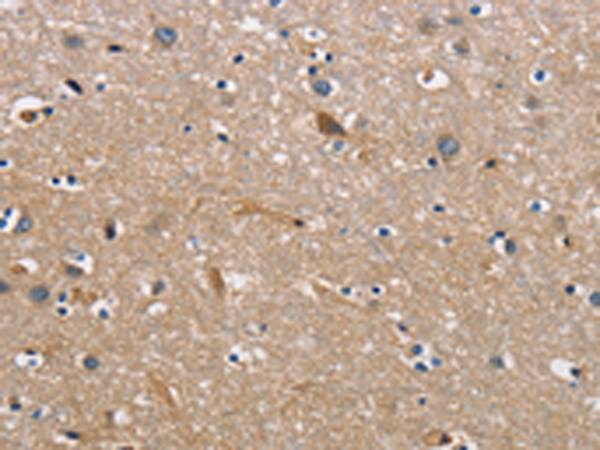

分类: 科研抗体货号: P07997别名: DFNB98; TSP-EAR; C21orf29应用: IHC反应种属: Human